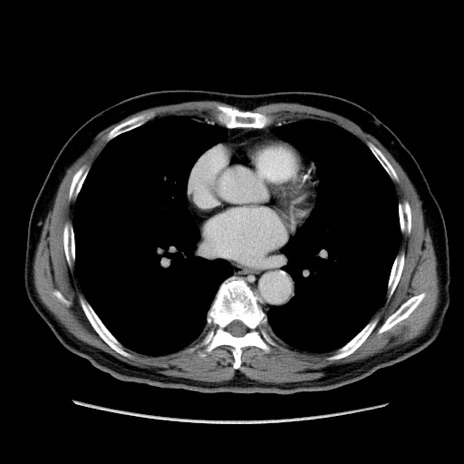

冠状断像